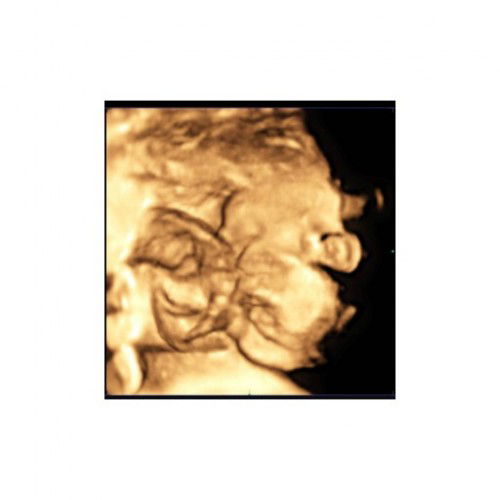

ซาวด์4Dก่อนคลอดตรงปกไหม

แม่ๆที่ ซาวด์4Dก่อนคลอดน้องตรงปกแบบในใบซาวด์ไหมคะ บ้านนี้ซาวด์4Dล่าสุด32wแม่หลงน้องไม่ไหวแล้วค่ะ ตอนนี้36+6wแล้ว 29พ.ย.นี้รอเจอตัวจริงอยากให้เป๊ะเหมือนในรูปค่ะ ♥️♥️